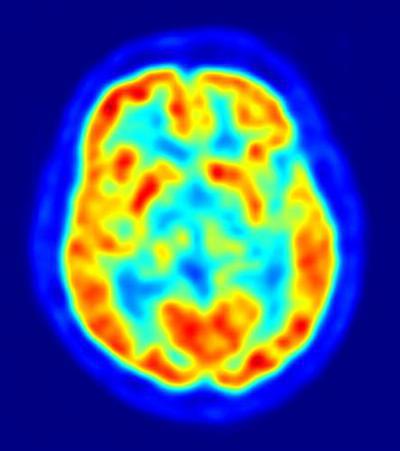

Las personas con facilidad para comprender a los demás son más altruistas; esta capacidad para comprender las perspectivas de otros ha sido previamente asociada con la actividad en una región del cerebro, conocida como unión temporoparietal (TPJ, por sus siglas en inglés). Basándose en estos hallazgos anteriores, Fehr y su equipo se dispusieron a analizar la relación entre el tamaño y la activación de TPJ, y las diferencias individuales en el altruismo.

En el nuevo estudio, los investigadores sometieron a los sujetos a un escáner de imagen cerebral, y les plantearon un juego en el que tenían que decidir cómo repartir dinero, entre ellos mismos y socios anónimos. Los sujetos que tomaron las decisiones más generosas mostraban un TPJ más grande, en el hemisferio derecho del cerebro, en comparación con los sujetos que tomaban las decisiones más egoístas.

"La estructura de TPJ predice con precisión el comportamiento altruista de un individuo", concluye el coautor del estudio, Yosuke Morishima, de la Universidad de Zurich.